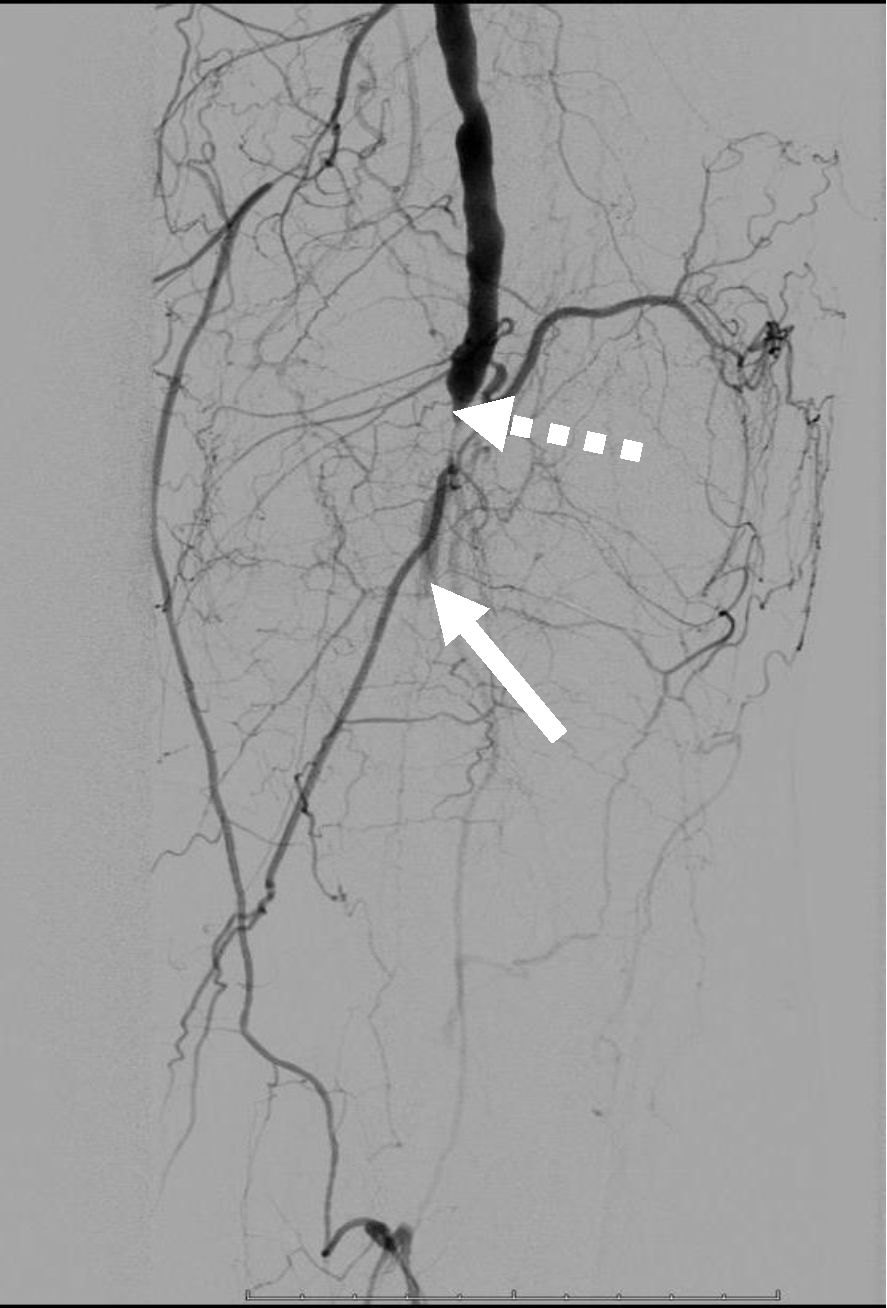

Операция. Транслюминальная баллонная ангиопластика (ТЛБАП) подколенной артерии, тибиоперонеального ствола слева. Под м/а выполнена пункция левой бедренной артерии, установлен интродьюсер 6 Fr. Выполнена селективная ангиграфия артерий левой нижней конечности при которой выявлена субокклюзия подколенной артерии и окклюзия тибиоперонеального ствола (рис. 1). Выполнена ТЛБАП в зоне субокклюзии баллоном 5,0 × 40 мм, давление 8 атм. В области тибиоперонеального ствола ТДБАП баллоном 3,0 мм × 100 мм, давление 10 атм. Получен хороший антеградный кровоток в подколенной, заднебольшеберцовой и малоберцовой артериях (рис. 2). Передняя большеберцовая артерия окклюзирована.

Рис. 2. Ангиограмма больной М. после ангиопластики. Восстановление магистрального кровотока в проксимальном (а) и дистальном (б) отделах голени

Послеоперационный период без осложнений. Со стороны раны положительная динамика, заживление вторичным натяжением.